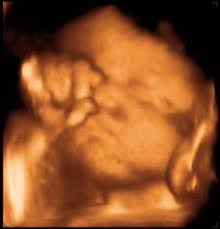

4d ultrasound is a 3d with the time aspect live video of the record. How your baby grows in pregnancy. A 4d ultrasound generates an image that is continuously updated much like a moving image. It is best to think of it with an example.

The main difference is that 3d focuses on the visual effects whereas 4d adds a tangible or tactile aspect to your movie experience. In 4d 3 4 images are taken per second which gives you an illusion of a movie. Or drops of water land on you when iron man flies by the bay. Difference between 3d and 4d images the four dimensional cube tesseract is one example of how the three dimensional world described by x y and z can extend into a fourth one.

3d and 4d ultrasound. A car has three dimensions. A 4d movie is a 3d movie with additional effects providing a real life experience emitted in special cinemas. 3d images are used to show you three dimensional external images that may be helpful in diagnosing issues such as a cleft lip.